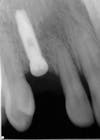

The life of your implants depends on your oral status and hygiene habits. With proper maintenance and regular professional cleanings, dental implants can last a lifetime. A dental implant replaces a missing tooth or anchors a bridge or denture. It has two parts: the implant post and the implant restoration. The post is a small, titanium screw placed into the socket left by a missing tooth. The implant post mimics a natural tooth root, providing a strong foundation for your final tooth restoration.

Dental implants are placed in our office almost as commonly as we place fillings. It is important that you see a dentist that places implants on a regular basis. It is also very important that your dentist utilize 3D imaging for the optimal placement of the implant. With 3D imaging we see where the most optimal bone is for the placement for each implant. The imaging also tells us where important landmarks are located that we need to preserve and avoid.